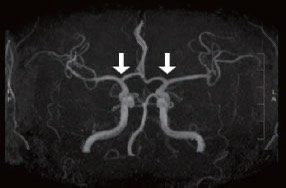

① 직접 우회술(Direct bypass)

• 측두동맥(STA)을 직접 뇌혈관(MCA)과 연결해 혈류를 즉시 공급하는 방식 • 성인에서 가장 많이 시행

• 수술 직후부터 혈류 개선 효과가 빠르게 나타납니다.